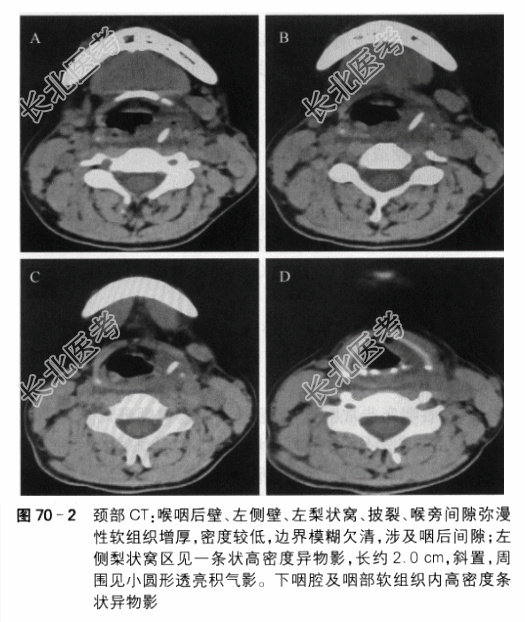

(3)颈部CT检查提示左侧喉咽部异物(主要位于梨状窝区)伴炎症感染(见图70-2)。